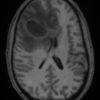

Apxe não

» Thông tin: Nam giới – 35 tuổi.

» Lâm sàng: Đau đầu.